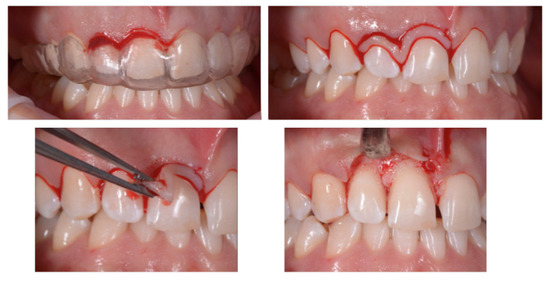

Case Report